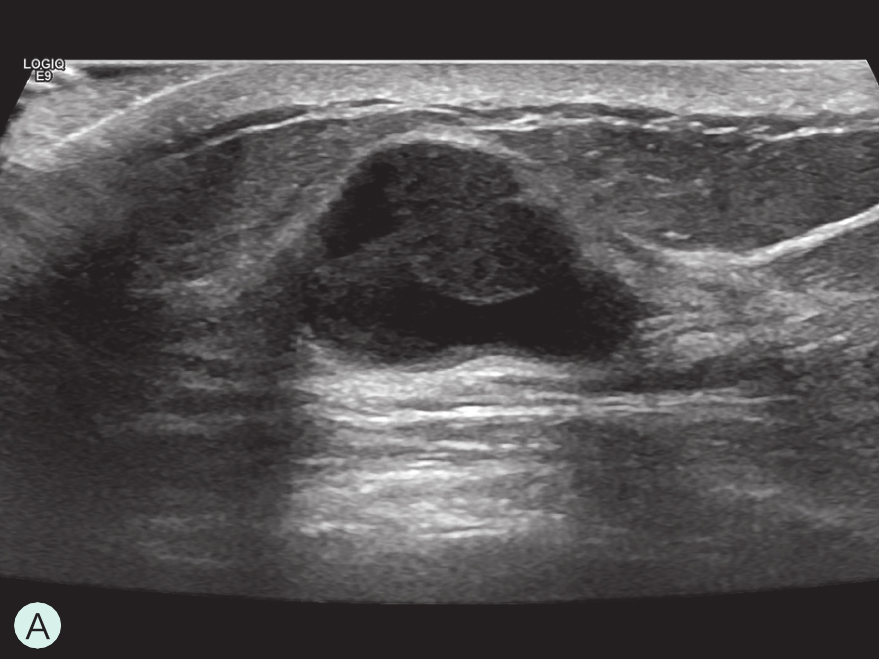

造影前应用传统灰阶超声全面扫查患侧乳腺及腋窝,重点扫查既往检查可疑病灶所在象限,结合既往检查确定超声造影靶目标及造影切面。评估病灶所在部位乳腺腺体致密性,二维及彩色多普勒(CDFI)超声常规检测肿块的大小、形态、边界、内部回声、血流及与周边组织的关系,充分利用现有超声新技术(如弹性成像)全面评估病灶。当病灶位置表浅、位于乳头后方或与探头耦合不佳时,可应用超声垫。

图2-2-1 确定造影病灶

A.病灶二维图像;B、C.病灶CDFI图像;D.同侧腋窝淋巴结情况;E.病灶弹性成像图像